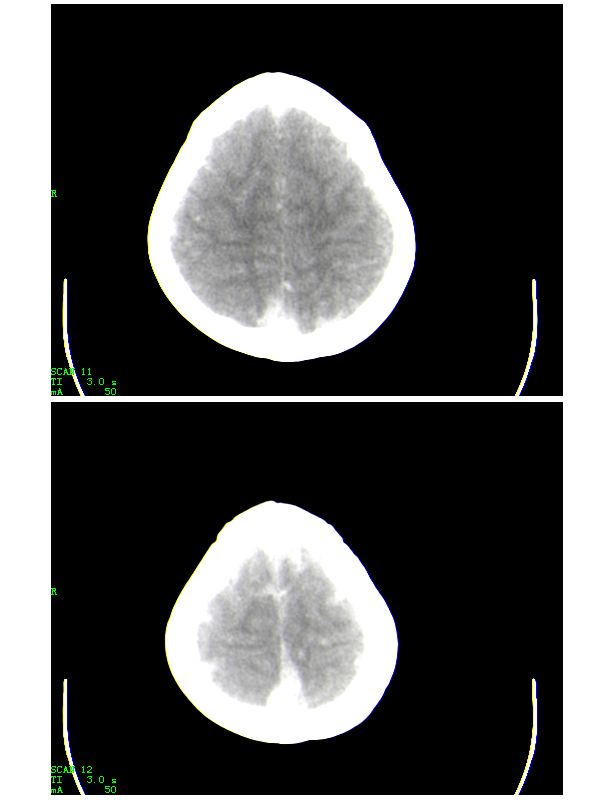

第五天的复查片

导致的原因楼上的战友已经讲的非常好了,再加深点印象

人体血液中影响ct值的主要成分是有形成分红细胞和血浆中的蛋白质,尤其室含铁的hb,其占血液中蛋白质总量的大部分,亦是引起血液ct密度变化的主要因素。hb含量与ct值间具有相关性,noman等的研究表明hb含量每改变10g/l,相应ct值变化为1.86hu。

本病主要应与蛛网膜下腔出血相鉴别,鉴别要点:

(1)高密度血管网络旁仍见清晰、正常低密度脑脊液影;

(2)临床没有急性颅内出血的症状何体征。